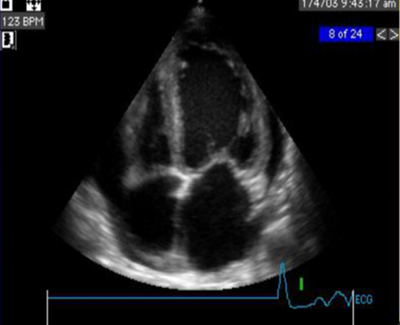

早期:心腔轻度扩大;

后期:各心腔均扩大;室壁运动普遍减弱;二、三尖瓣反流